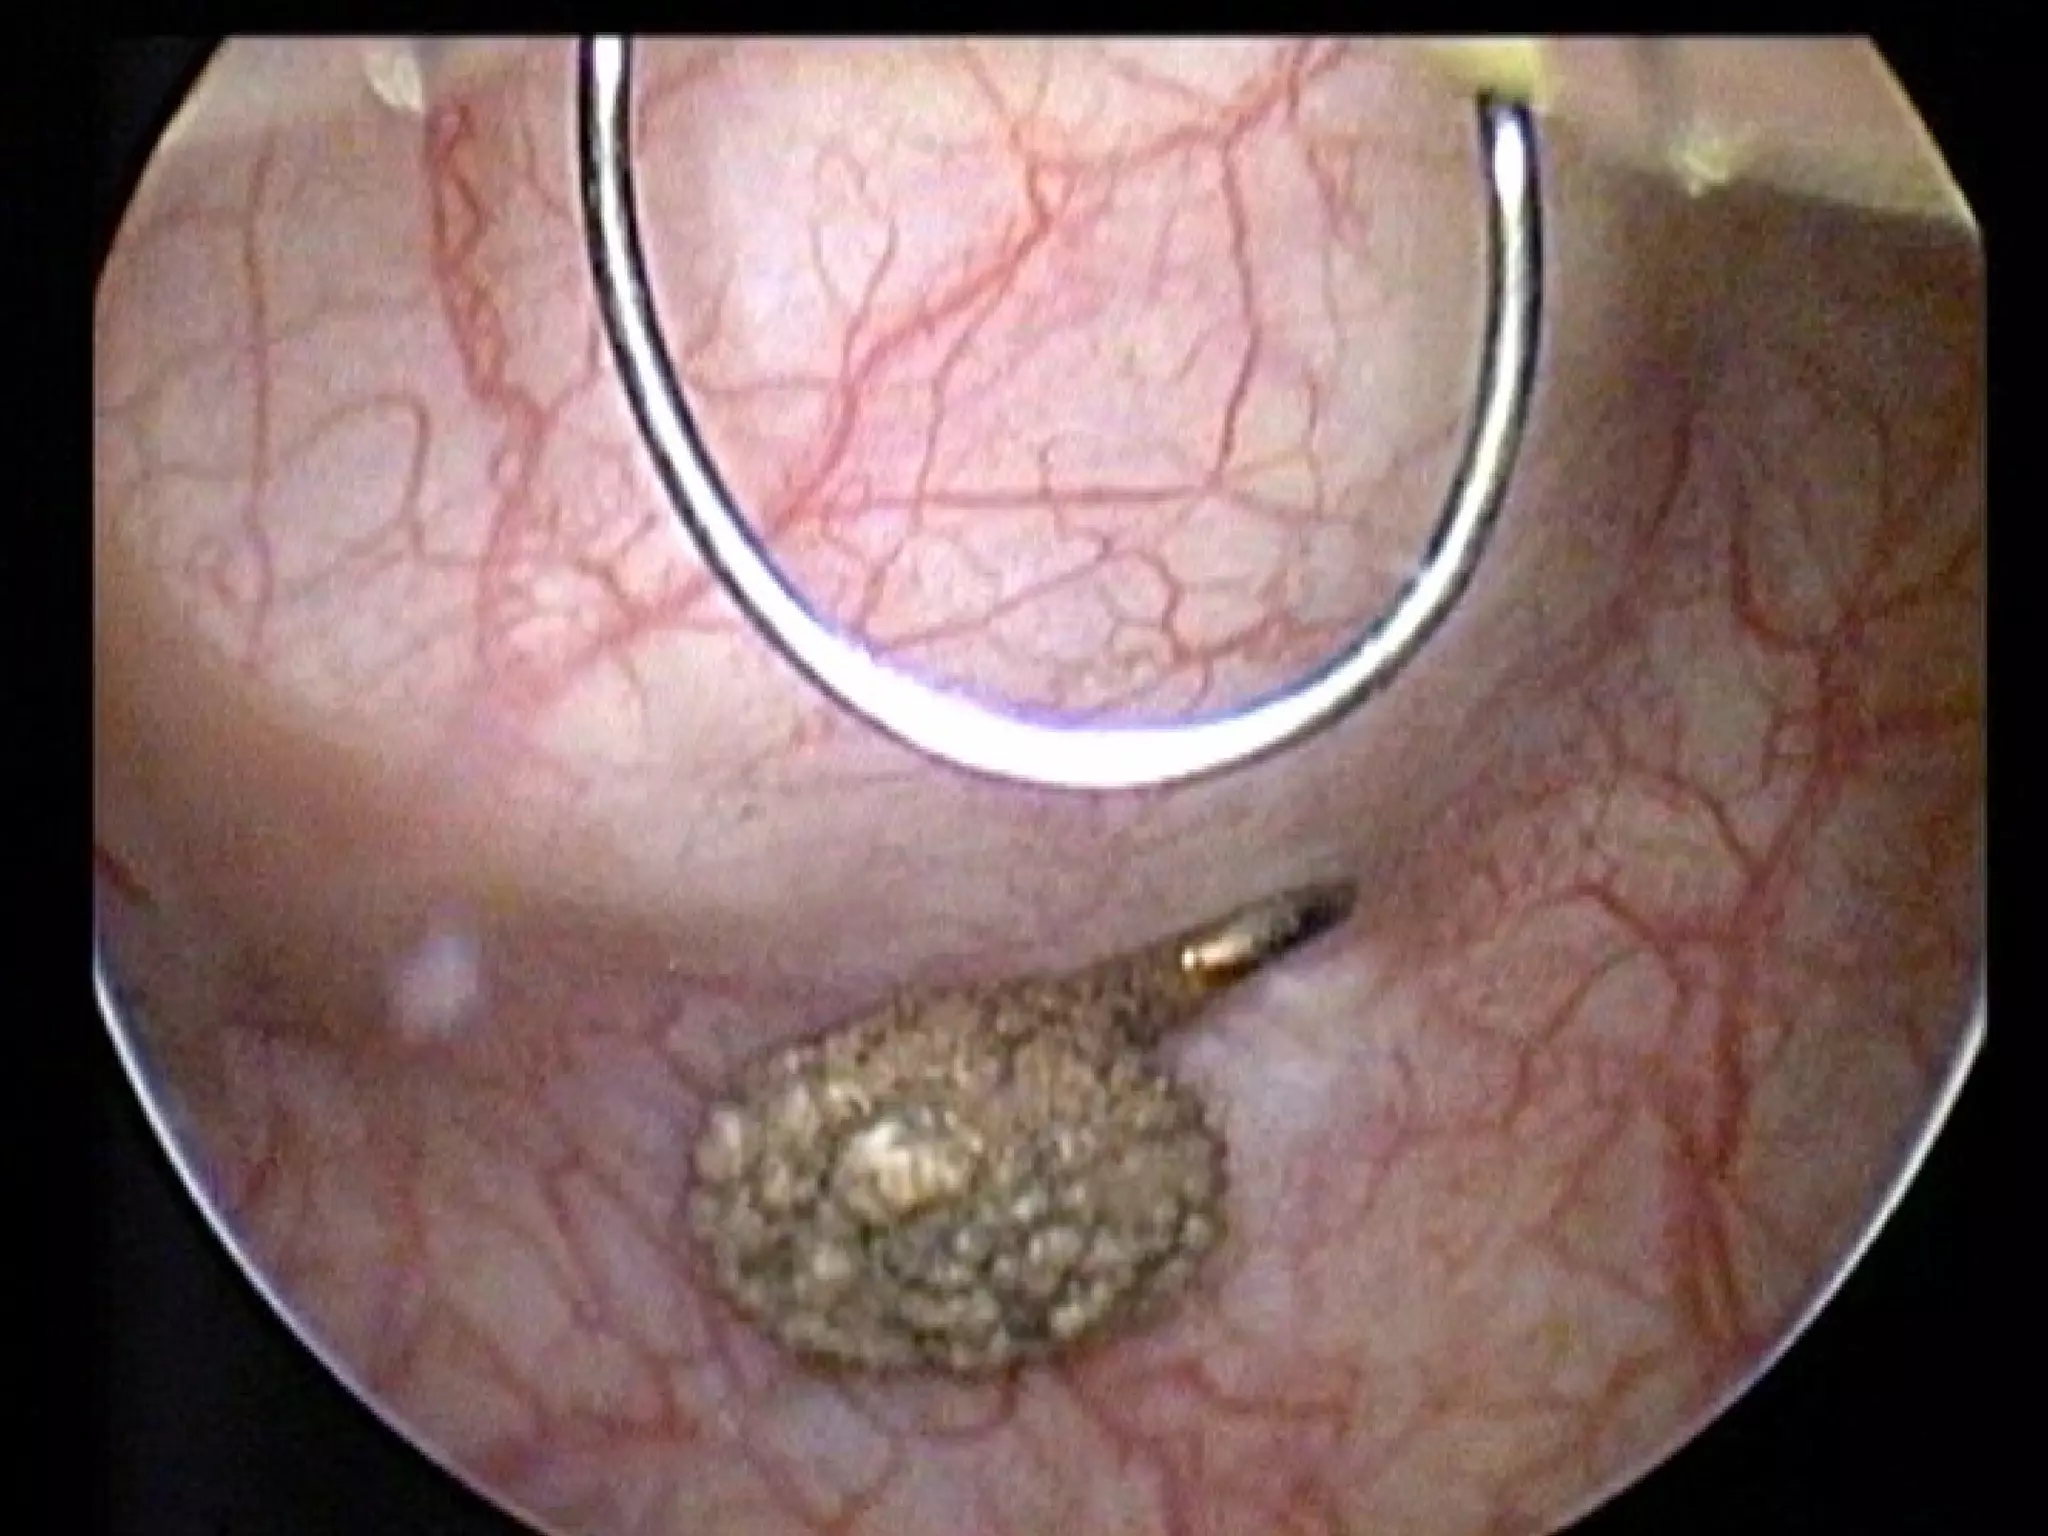

Components Separation Developed by Dr. Ramirez in the late 80’s Employs the use of autologous myofascial tissue to effect abdominal wall closure Bilateral relaxation incisions 2cm lateral to the external oblique from costal margin to level of symphasis pubis Blunt separation of external oblique layer from underlying internal oblique layer taking care not to interrupt vascular/nerve supply May employ undermining of one or both posterior rectus sheaths to achieve further medial advancement **Provides dynamic support of the abdominal girdle**

Components Separation